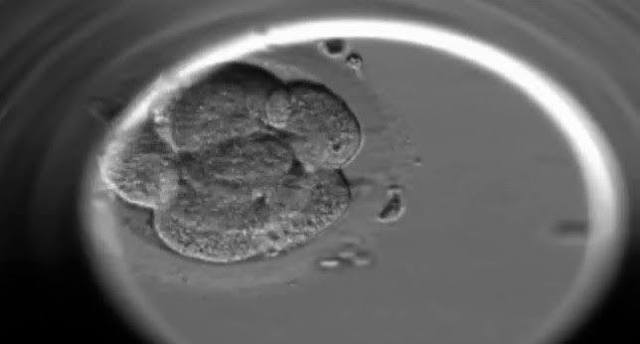

• Nace el primer bebé de probeta

Nace el primer bebé de probeta

Nace en gran Bretaña el primer bebé probeta, engendrado mediante fertilización artificial o in vitro.